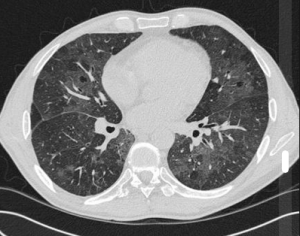

Radiology Quiz

Dr Anna Gerratt shared some xrays and CT images of smoking-related pathology. Examples included:

- Apical bullae due to cannabis smoking

- Classical emphysema due to tobacco smoking

- Emphysema with fibrosis (CPFE) due to tobacco smoking

- Pneumothorax, a complication of bullae

- RB-ILD

For examples see Radiopedia